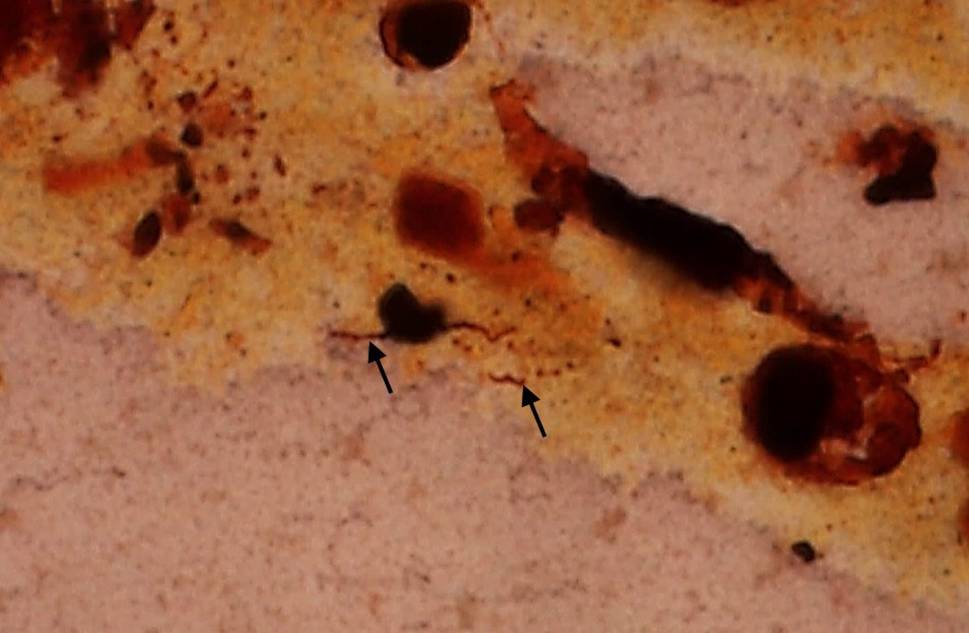

Fig. 2

Serosa of the colon covered by fibrin interspersed with neutrophils (arrows). Hematoxylin and eosin, original magnification 200 ×

The peritoneal cavity contained 150 mL of turbid fluid. The liver was enlarged with a coarse border and multiple irregularly distributed bright yellow areas in the liver capsule (suspicious of ischemic areas). It weighed 2.5 kg. Histology showed massive steatosis (grade 3) with moderate inflammatory infiltration of the portal fields, and portal and focal septal fibrosis (stage 1), but no evidence of viral hepatitis (Fig. 1). The serosa of the bowel was covered and clotted with fibrin; histology showed massive infiltration with neutrophils and multiple bacteria, mainly of coccoid structure, which is typically found in fibrinous-putrid peritonitis (Fig. 2). The kidneys appeared normal on gross examination and displayed focal interstitial lymphocytic infiltration and mild arteriosclerosis on histology. The spleen, pancreas and stomach were macroscopically and histologically unremarkable.